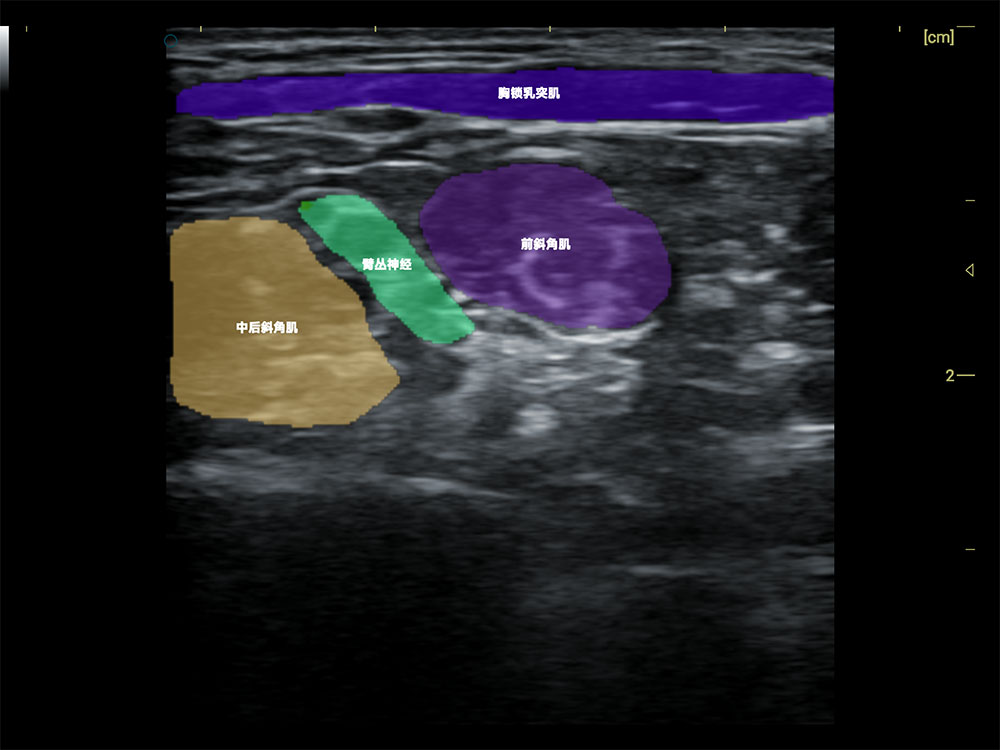

• AI 智能识别甲状腺病灶

• AI 辅助诊断,提速降错